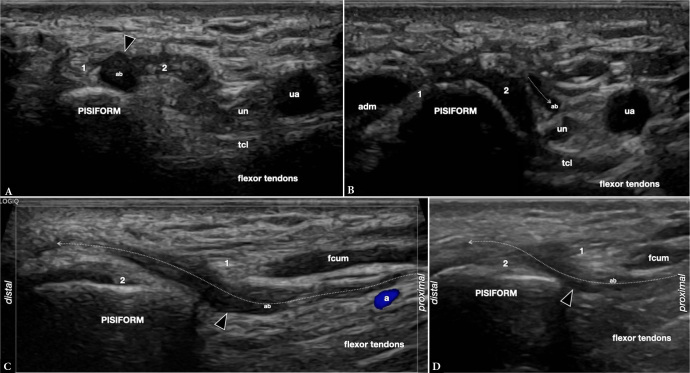

Results: Between October 2019 and October 2023, six cases were found in five patients, where ultrasound demonstrated previously undescribed-at-imaging anatomical variations of the distal ulnar nerve on six distal forearms. The variant was symptomatic in three cases in which possible distal compression was clinically suspected. A branch of the ulnar nerve made a loop around the flexor carpi ulnaris, which also presented with a variation of normal anatomy. In symptomatic patients, the diameter of the aberrant branch (retrospectively measured) was significantly enlarged.

Conclusions: High-resolution ultrasound can accurately demonstrate ulnar nerve variants even when only small nerve fascicles are involved, which may be clinically relevant and misinterpreted. Loops of the ulnar nerve are rare, but likely under-recognized. We think that symptoms are generally tolerated by patients if the motor branch of the ulnar nerve is not affected, as in our cases.